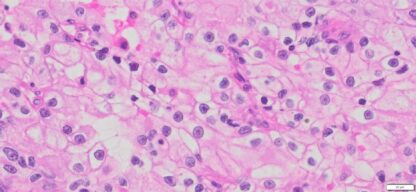

Description

| HuPS-05002T1 | Kidney | Clear –cell renal cell carcinoma | No | Male/56 | 75% | III | pT1apNxMx | NA |